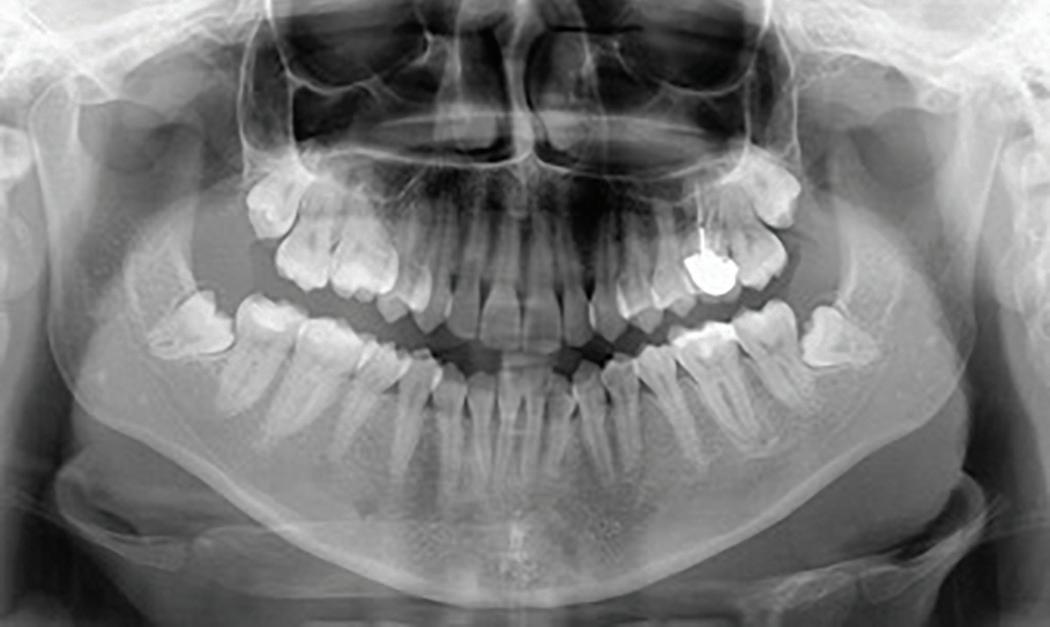

Root migration after coronectomy of impacted mandibular third molars: case reports

Jéssica Lemos Gulinelli

Pâmela Leticia dos Santos